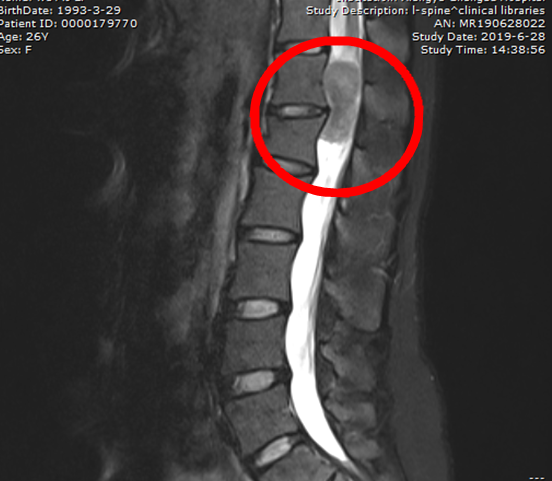

26岁的伍女士一直都有腰背部疼痛的毛病,但就在3个月前,她突然感到腰背部的疼痛逐渐加重,同时右下肢也开始疼痛、麻木,甚至出现持续性胀痛,尤其在夜间休息时、久坐、久站后疼痛格外明...